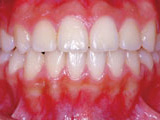

症例2:乱ぐい歯「歯並びが乱れている」

治療前 治療後